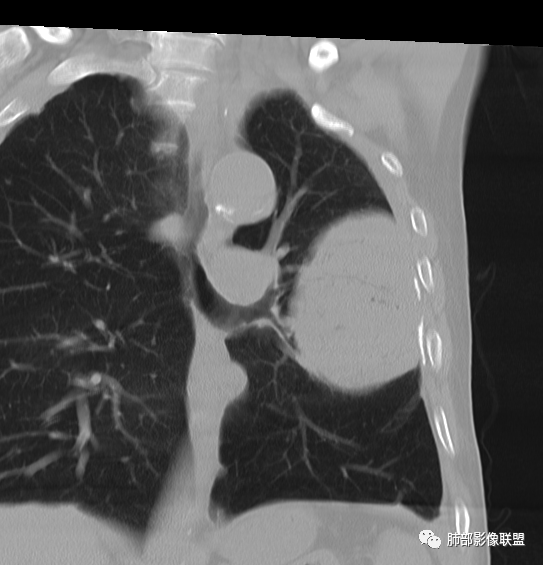

左肺上叶大肿块,膨胀性生长,边界清,密度较低,见部分坏死区,强化弱,肿块见支气管充气V扩张征,分布僵直,枯树枝特点,另一个重要特点血管造影征,淋巴瘤,肿块长轴与胸膜平行,与隐球菌鉴别,隐球荚膜抗原检查,明确诊断经皮肺穿刺。另胸膜钙化(问诊既往有无患胸膜炎病史)。

左肺上叶胸膜下肿块,宽基底与胸膜相连,跨叶裂,边缘清晰膨隆,其内支气管充气,部分扩张、僵直,无明显强化,血管造影征,考虑淋巴瘤,鉴别腺癌

左肺胸膜下巨大占位,跨叶裂,宽基底与胸膜相连,胸膜钙化,平扫密度较低,强化不明显,可见内部血管显影,支气管充气征和扩张,考虑为恶性,倾向于淋巴瘤

左侧胸腔巨大肿块,跨叶生长,临近胸膜钙化,边缘模糊,可见支气管影,定位肺内,增强后轻度强化,边缘见血管影,考虑淋巴瘤,鉴别肉瘤

左肺上叶胸膜下肿块,膨胀性生长,边界清晰,密度不均部分坏死,未见强化,病灶内支气管迂曲扩张,病灶长轴与胸膜平行,胸膜下脂肪间隙存在,胸膜钙化,考虑放线菌?毛霉?鉴别淋巴瘤

支持淋巴瘤,左上肺大肿块,有分叶,边缘光整,病灶内密度不均,可见支气管扩张征,增强后可见血管影征。周围肺野清晰。

左肺上叶肿块,宽基底与胸膜相连,跨叶裂,边缘清晰膨隆,可见小分叶,其内支气管充气,部分扩张、僵直,呈枯枝征,支气管达边征,增强无明显强化,可见血管造影征,考虑恶性病变,淋巴瘤,鉴别粘液腺癌。

大肿块,边缘光滑,深分叶

近端支气管堵塞、推移为主

部分类似于脐凹征

内部支气管扩张

肺动脉推移为主,边缘部分进入

1)部位:周围型或中央型软组织肿块,以周围型为多见,且肿瘤多位于肺上叶。如本例:该肿瘤位于左肺上叶。

2)大小及形态:由于本病恶性程度高,早期症状不明显,发现时肿块均较大。如本例病变巨大。

3)肿块边界和边缘:多较清楚,呈圆形、类圆形,且由于肿块生长速度不均匀,可见分叶,毛刺少见。有报道肿块周围毛玻璃影是多形性癌特征表现。